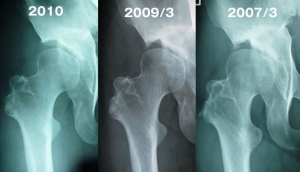

骨の変化(2008年の写真はみあたらず)

段差のあった骨の結合部がなめらかになってきています。

人体ってすごいね。